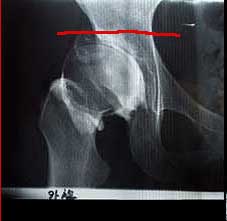

右の股関節X線です。赤い線のところで骨盤を二つに切ります。ノミやノコギリ?を使うようです。

そして切った部分を左右にずらし、足りない”かぶり”を人工的に大きくする。